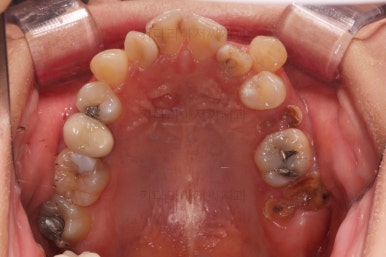

초진 시 입안의 모습입니다.

이미 썩어서 부러진 치아도 몇 개 보이고요.

많이 삐뚤어진 치아쪽은 양치가 힘들어 이미 많이 썩어 있는 상태에 덧니쪽은 잇몸도 많이 내려간 상태였습니다.

말그대로 교정치료 뿐만 아니라 전반적인 치료가 필요한 상황이었습니다.

하지만 이번 환자분은 매우 삐뚠 앞니쪽에 충치가 있었기 때문에 급한대로 신경치료만 하고 임시로 떼워놓고 가지런하게 된 뒤에 최종적으로 심미보철을 진행하기로 했습니다.

현재 모습대로 보철을 한다면, 공간부족으로 치아 크기가 예쁘게 안나오고 삐둔 형태대로 모양이 만들어져서 자칫하면 가지런하게 된 뒤에 모양이 매우 못나 보일 수 있기 때문이죠.

충치치료르 한다고 몇 달을 기다리다 보면 교정 후에 해야 하는 충치는 더 늦어지기 때문에 우선 교정장치부터 부착하고 충치치료는 병행해 가면서 하기로 했습니다.